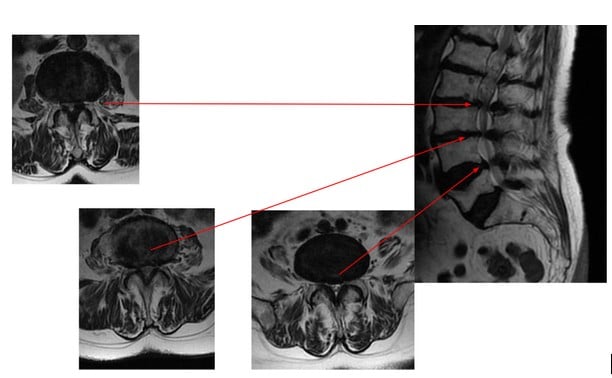

Wielopoziomowa stenoza w obrębie segmentu ruchowego L2/L3, L3/L4 i L4/L5

W przebiegu choroby zwyrodnieniowej ucisk na struktury nierzadko występuje na 2 albo i 3 poziomach. W swojej praktyce lekarskiej napotkałem na przypadki wielopoziomowej stenozy (ciasnoty) kanału kręgowego w obrębie segmentów ruchowych kręgosłupa na poziomach L2/L3, L3/L4 oraz L4/L5. Dlatego w czasie prezentacji omówiłem przypadek 82-letniej pacjentki, u której zwężenie kanału kręgowego prowadziło do znacznego ucisku na struktury nerwowe, wywołując dokuczliwe objawy w zakresie bólu i ograniczenia ruchomości.

Na zdjęciu wykonanym przed zabiegiem widoczna wielopoziomowa ciasnota w obrębie segmentu ruchowego L2/L3, L3/L4 i L4/L5